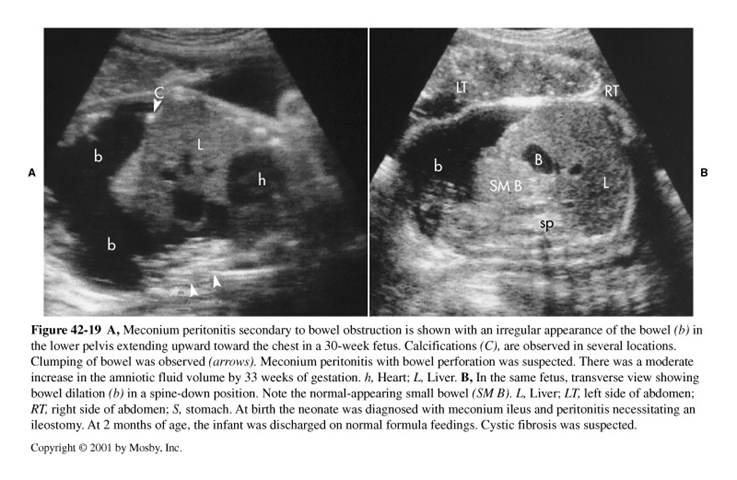

What is this image showing?

Meconium Peritonitis

Obstructed Bowel may perforate and = ____________ __________

What is meconium peritonitis?

An inflammatory response from leakage of bowel contents, causing fibrosis of tissue & calcifications

Pseudocyst may develop because of chronic peritonitis